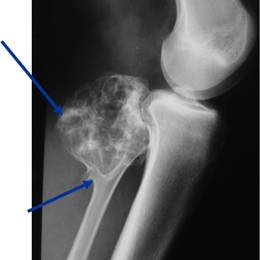

Radiographic imaging is used to help form a diagnosis. These include X-Ray, MRI, CT and Bone Scans

An example of an Osteochondroma MRI is shown.